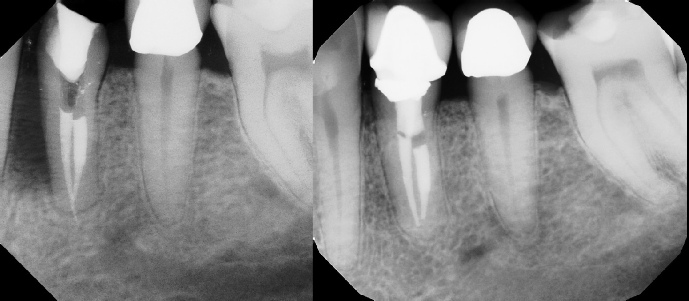

COMPLICATED ANATOMY LARGE LESIONS CALCIFIED CANALS PERFORATION / RESORPTION SEPARATED INSTRUMENTS SURGICAL CASES RETREATMENT / pOST REMOVAL OPEN APICES ACCESS THRU CROWNS Root Canal Case Portfolio

Pre-op Post-op 6 mos.